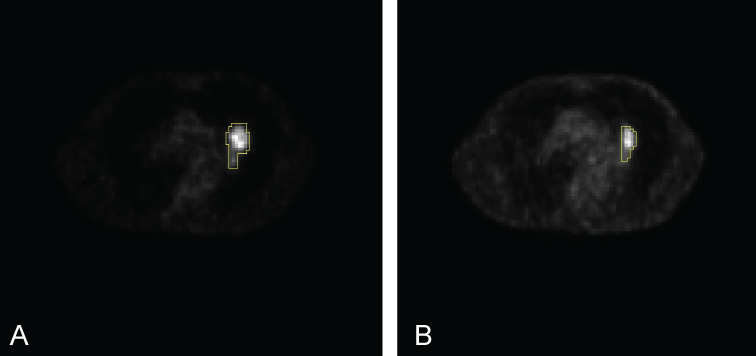

[18F] Fluoro-2-Deoxy-2-Dglucose (18F-FDG), a glucose metabolism analog used as the PET tracer has been frequently applied in clinical practice for tumor detection, staging, and radiotherapy target definition of different cancer sites [4]. FDG-PET showed moderate sensitivity and specificity for the detection of locoregional metastases, and reasonable sensitivity and specificity in detection of distant lymphatic and hematogenous metastases [5]. There is enough evidence showing that FDG uptake value could be used as an important index to measure cancer therapy effect [6]. In the last 5 y, PET/CT has also gained widespread acceptance as a key tool used to demonstrate early response to intervention and therapy [7]. In this paper we mainly concentrate on assessing the response to CRT in lung cancer. A visual pattern analysis technique was applied in Hicks, et al. [8] for grading tumor response and normal tissue toxicity in patients with Non-Small Cell Lung Cancer (NSCLC) (Figure 1A and Figure 1B). Several studies also have evaluated the role of PET in predicting treatment response based on 18F-FDG uptake changes between a pre- and a post-treatment PET scan obtained during or after treatment completion [9,10]. If accurately assessing is conducted we can firmly determine that the therapy program is effective or the program is not suitable for the patient's treatment. However, the single Standardized Uptake Value (SUV) measurement change in pre-therapy and treatment completion PET scans is potentially impacted by the initial FDG uptake kinetics and radiotracer distribution, which are dependent on the initial dose and elapsing time between injection and image acquisition [11-13]. Alternatively, there have been some efforts in the literature directing towards utilizing variations in the FDG distribution, characterized by its heterogeneous shape and texture [14].

Figure 1: PET scans for a selective NSCLC patient. The clinical tumor volume were outlined by yellow line, respectively, scan A) for pretreatment and B) for one month after treatment completion. Note the tumor volume shrinked after CRT treatment comparing A and B. View Figure 1